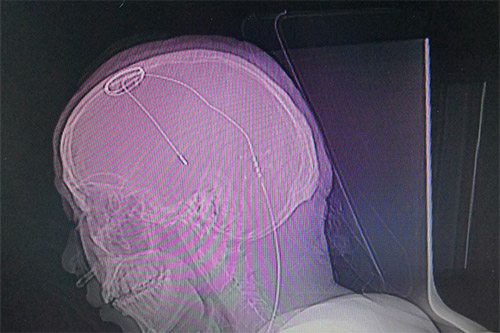

▲患者植入腦起搏器后的影像圖

準(zhǔn)備就緒后,醫(yī)生利用磁共振(MR)結(jié)合立體定向設(shè)備為患者進(jìn)行影像掃描,再利用手術(shù)計(jì)劃系統(tǒng)進(jìn)行數(shù)據(jù)計(jì)算,規(guī)劃手術(shù)路徑,確定手術(shù)的三維立體精準(zhǔn)坐標(biāo)。“電極的直徑只有1毫米左右,對(duì)手術(shù)定位精準(zhǔn)度要求非常高,哪怕一點(diǎn)誤差都會(huì)影響治療效果。”將手術(shù)坐標(biāo)與患者頭部定位支架核對(duì)確定后,劉偉欽主任及其團(tuán)隊(duì)在患者頭部切開了一道切口,并在顱骨打孔,固定好電極基環(huán),最后將電極緩緩植入大腦內(nèi)丘腦底核處。

電極到達(dá)預(yù)定位置后,劉偉欽主任對(duì)患者進(jìn)行感覺和運(yùn)動(dòng)測(cè)試,以直觀地評(píng)估電極工作情況;颊哒f話清晰,視力視覺無影響,四肢活動(dòng)自如,手腳抖動(dòng)消失,手術(shù)效果令人滿意,然后對(duì)電極位置進(jìn)行固定。隨后對(duì)患者進(jìn)行全身麻醉,將導(dǎo)線經(jīng)過耳后皮下隧道與置于鎖骨下皮下的電池連接固定。術(shù)后行CT掃描,將CT掃描數(shù)據(jù)導(dǎo)入手術(shù)計(jì)劃系統(tǒng)融合、計(jì)算,電極與預(yù)設(shè)手術(shù)路徑完全吻合,位置準(zhǔn)確無誤,手術(shù)無出血,手術(shù)順利完成。